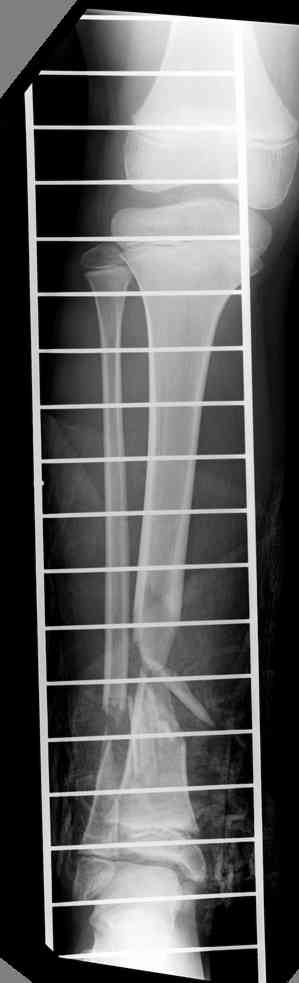

-->> дистальный фрагмент слишком короткий, меньше 2 см, нет места для интрамедуллярного штифта, в отличии от пациента Др. Иванова (прекрастный результат!).

Another choice is simply perform shortening + posterior angulation with Ilizarov or TSF , than gradual correction of the angulation.After all apply third ring on the proximal tibia and start lengthening.

We had recently similar case in 14 years old boy with 45 mm bone defect after open tibial fracture.Boy doing excellent .This technique is not new, Sasha Lerner did it in Rambam , Rozbruch wrote also.

> Another choice is simply perform shortening + posterior angulation

> with Ilizarov or TSF , than gradual correction of the angulation.

Действительно, если есть длинная косая линия на проксимальном отломке, это жалко будет не использовать. Можно сделать коррекцию угла не обратным разведением фрагментов, а оставить их в контакте, и сделать кортикотомию проксимальнее на 2-3 см. Можно и сейчас отсечь такой фрагмент и транспортировать его с разворотом. Наверно, вариант с ангуляцией более технологичен.

Да, надо удалить все железо, сделать для ангуляции остеотомию малоберцовой на уровне дефеормации, а после восстановления оси сразу освободить стопу. То есть в дистальном отломке tibia надо побольше

спиц с упорами, а на диафизе только half-pins с передне-внутренней стороны, чтобы как можно меньше пострадала передняя группа мышц.